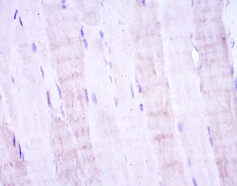

This gene encodes a dual specificity protein kinase that belongs to the Ser/Thr protein kinase family. This kinase is a direct activator of MAP kinases in response to various environmental stresses or mitogenic stimuli. It has been shown to activate MAPK8/JNK1, MAPK9/JNK2, and MAPK14/p38, but not MAPK1/ERK2 or MAPK3/ERK3. This kinase is phosphorylated, and thus activated by MAP3K1/MEKK. The knockout studies in mice suggested the roles of this kinase in mediating survival signal in T cell development, as well as in the organogenesis of liver.Tissue specificity: Abundant expression is seen in the skeletal muscle. It is also widely expressed in other tissues .

IHC    1/200 - 1/1000